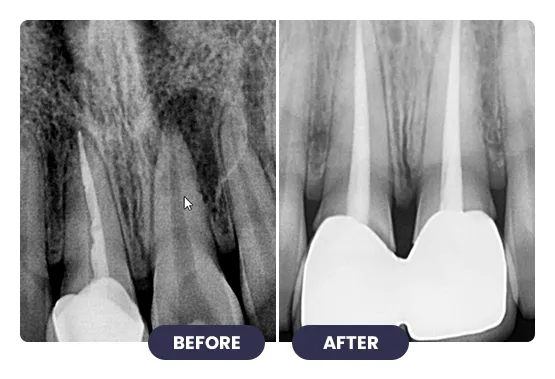

Treating infected or damaged teeth with root canal treatment at iCube Dental is a precise, technique-sensitive procedure that requires professional expertise and careful planning.

Advanced tools and methods are used to remove infection, clean the tooth canals, and restore tooth structure. This treatment relieves pain, prevents further infection, and preserves your natural tooth, ensuring proper bite and chewing function.

With expert care at iCube Dental, root canal treatment is safe, effective, and designed for long-lasting results – helping you maintain oral health and a confident smile.